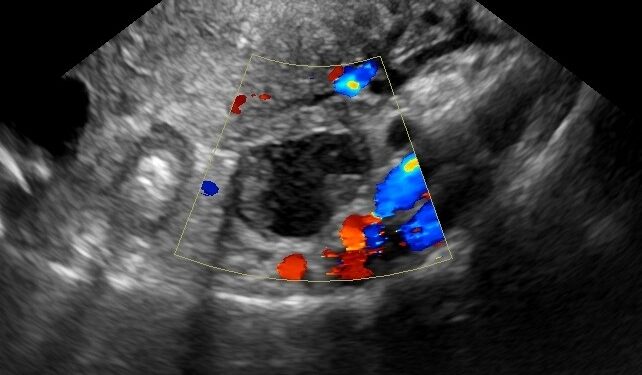

The study, published Thursday in JAMA Network Open and supported by grants from the National Cancer Institute, examined the CA-125 test, a common diagnostic tool. This test measures tumor markers in the blood and helps doctors decide whether a woman with a suspicious lump should be referred to a cancer specialist.